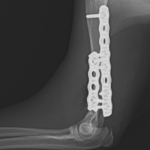

上腕骨遠位粉砕骨折

若い猫ちゃんが部屋で遊んでいたところ、不運にも上腕骨を粉砕骨折してしまったとのこと。かかりつけ医から固定術の依頼がありました。粉砕部分をOrthogonal Plateで固定術を行いました。

リハビリと安静期間をしっかり守って、早く元気に走れるようにサポートしていきます。